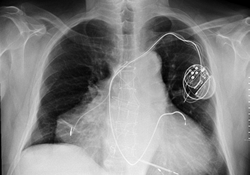

А 7 ноября его положили в больницу. ЭКГ при поступлении - ритм синусоидный регулярный. ЧСС 80 уд.в мин. ІІ, ІІІ. АVF. V3-V6 отрицательный з.Т. При этом сердце не болело. Прошел лечение. ЭКГ при выписке -ритм синусовый, регулярный, ЧСС 67 уд.в мин. О-негативный инфаркт миокарда задне-боковой области левого желудочка с вовлечением верхушки ЛЖ. Ст. Рубцевания. Рекомендовано проведение кардиографии. Выписали из больницы 18 ноября. Появились боли в сердце , не очень интенсивные, но периодически возникающие, колющие. Посоветуйте с чего надо начинать. КАк поступить если оба заболевания угрожают жизни. Что в этом случае является первичным. Существуют ли медучреждения , где возможно одновременное участие специалистов по этим заболеваниям. Какие исследования еще необходимо выполнить для определения тактики лечения. Анализ крови от 7.11.08г. -Эр 4,22, Нb-159, Л- 8,2, СОЕ -18, сахар -3,1. Протромбированное время 24с, индекс- 87%, фибриноген 3.55. Биохимия крови от 10.11.08г АлАТ 1,16, АсАТ 0,5, К-4,9, Na -137,креат. 90. мочевина 6.2. Биохимия крови от 13.11.08 АлАТ -28,2 ед/л, АсАТ -14.9 ед/л.

Диагноз при выписке. Осн. ИБС. острый О-негативный инфарки миокарда задне-боковой области левого желудочка с вовлечением верхушки. Диффузный кардиосклероз. Гипертоническая болезнь ІІ (гипертензивние сердце). Постифарктная стенокардия. Осл. СН ІІ А. ФК ІІ. Соп. Смешанній зоб 1-11 ст. эутиреоз. В настоящее время продолжаемпить назначенные лекарства. Оставляю телефон, разговор за мой счет. Может кто-то откликнется. 8 050 328 72 23